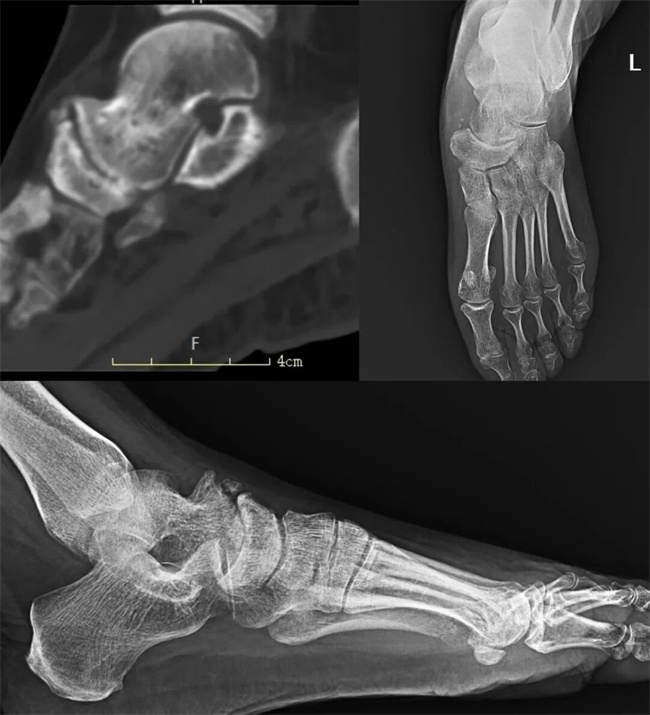

二、患者武某某,男,50岁,患者右踝部肿胀疼痛,走路跛行,踝关节周围肿胀,外踝及距舟关节压疼明显。为求进一步治疗,来到我院请专家会诊,通过各位专家会诊查体、查看影像资料并细致认真的分析后,诊断为:距舟创伤性关节炎,意见:关节融合术。